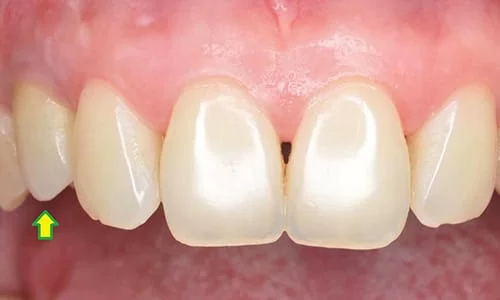

植牙假牙裝置後

患者本身來門診時,乳齒搖動度已相當大,僅殘根黏著於牙齦處,故並無任何咬合及飲食功能,對患者本身的生活造成了影響及困擾。且因乳牙本身型態過小、不佳並且搖動,以至於患者不敢露出牙齒笑,也間接影響了人際互動關係。

在植牙重建美觀及咬合功能後,對於病患來說,除了可以正常飲食之外,也對其自信心產生了極大的鼓勵。

我只能說真的很謝謝醫師當初告訴我可以用植牙的方式來處理這個問題,是不是很漂亮呢?完全看不出來哪顆是植牙唷!我以前去家裡附近的診所,醫生都說要把我前後的牙齒磨小做假牙,但是我真的會捨不得!現在我不但保留了原本好的牙齒,還可以吃排骨!更敢大聲笑了!同事都說我變得很開朗!簡直是變了個人呢!